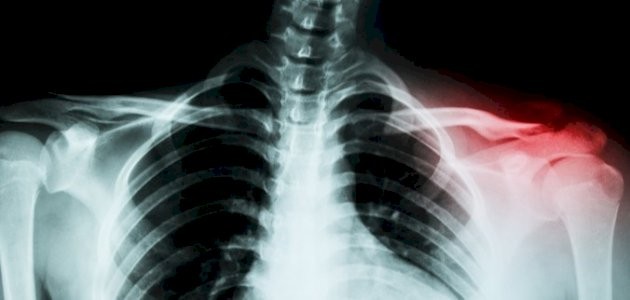

ويعرف عظم الترقوة بأنه العظم الطويل النحيف الموجود في الجزء العلوي من الجدار الصدري أسفل العنق وعلى جانبي عظمة الصدر.

3. كسر عظم الترقوة

ستعرف كسر عظم الترقوة إذا بدأ الألم حول المنطقة فجأة وازداد مع محاولتك التحرك.

وقد تشعر أيضا أو تسمع صريرا أو نقرا، وتواجه ألما أو تورما أو كدمات أو تصلب الذراع.

وقد تكون حالة تسمى انحلال العظم الترقوي القاصي أيضا سببا في التهاب عظم الترقوة، ويحدث هذا عندما تتطور الكسور الصغيرة في نهاية الترقوة الأقرب إلى الكتف.